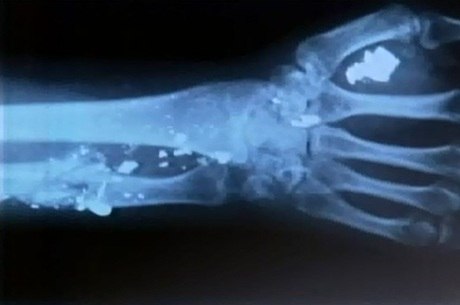

Os problemas são reflexos da bala alojada na coluna. Ele foi vítima de uma tentativa de assalto há cerca de um ano e foi alvejado três vezes. Dois disparos atingiram as costas e outro a mão do pintor.

Mesmo socorrido, os médicos não retiraram nenhuma bala do corpo de Ivan. Por causa do projétil que está perto do polegar, o homem de 42 anos perdeu alguns movimentos da mão e como sempre trabalhou como pintor, teve que aprender outra função para sustentar a família. Ele conta que hoje vive com o que ganha lavando carros.

Segundo o pintor, especialistas já disseram que as balas alojadas nas costas não podem ser retiradas porque são procedimentos de alto risco. Mas ele espera que a da mão seja removida, já que recebeu um encaminhamento médico, mas, há quase oito anos, espera uma resposta.